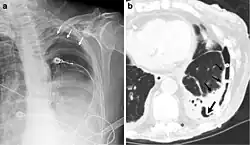

El diagnóstico del fibrotórax suele basarse en una historia clínica adecuada combinada con técnicas de imagen como la radiografía de tórax o la tomografía computarizada.[3] Estas herramientas detectan el engrosamiento pleural y la fibrosis alrededor de los pulmones.[7] La presencia de una corteza engrosada, con o sin calcificación, es una característica común en las imágenes.[3] Las tomografías computarizadas diferencian mejor si el engrosamiento se debe a depósitos de grasa o a fibrosis verdadera.[3]

En casos graves, el pulmón afectado puede perder volumen[7] y el mediastino puede desplazarse hacia el lado afectado.[3] Una reducción del tamaño de un lado del tórax en las imágenes sugiere cicatrización crónica.[6] Los signos de la enfermedad subyacente que causa el fibrotórax también se observan ocasionalmente en la radiografía.[6] Las pruebas de función pulmonar suelen mostrar hallazgos compatibles con una enfermedad pulmonar restrictiva.[6]

Fibrotórax extenso en el lado izquierdo. -

Radiografía de tórax que muestra opacidad heterogénea en la mitad izquierda del tórax por fibrotórax. -

Radiografía de tórax (izquierda) y tomografía computarizada (derecha) que muestran fibrotórax. -